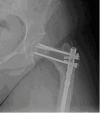

The use of humeral nails for femoral subtrochanteric fractures is rarely reported. We present a case in which a humeral nail was employed for a subtrochanteric femur fracture alongside contralateral prophylactic stabilization of the femoral neck and shaft. A 29-year-old female patient with a history of bilateral varus-producing proximal femoral osteotomies, complicated by symptomatic hardware indicating bilateral removal, sustained a subtrochanteric fracture. Given her 98-degree neck-shaft angle, a humeral nail was selected for right femur fixation. She also underwent prophylactic stabilization of the contralateral proximal femur with a humeral nail. There are limited options for addressing subtrochanteric femur fractures in patients with anatomy variations that preclude using standard femoral nails. This case demonstrates the successful off-label use of a humeral nail for subtrochanteric femur fracture when a traditional femoral nail is impossible.